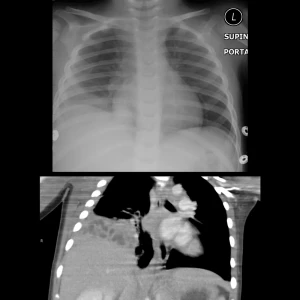

La progresión de la enfermedad atraviesa tres fases fisiopatológicas críticas que dictan la agresividad del tratamiento. Iniciamos con una etapa exudativa de líquido estéril que puede responder solo a antibióticos, seguida de una etapa fibrinopurulenta caracterizada por la invasión bacteriana y el depósito de fibrina que forma tabiques o septos, y culminamos en una etapa de organización donde los fibroblastos crean una corteza fibrosa que atrapa el pulmón, limitando su expansión. Para confirmar el diagnóstico, la toracocentesis es esencial, revelando marcadores bioquímicos de mal pronóstico como un ph inferior a 7.2, glucosa menor a 40 mg/dl y una ldh superior a 1000 ui/l. En cuanto a la imagenología, la ecografía a pie de cama es la herramienta de elección por su superioridad para detectar loculaciones, mientras que la tomografía con contraste puede mostrar el signo de la pleura dividida, confirmando el engrosamiento pleural.